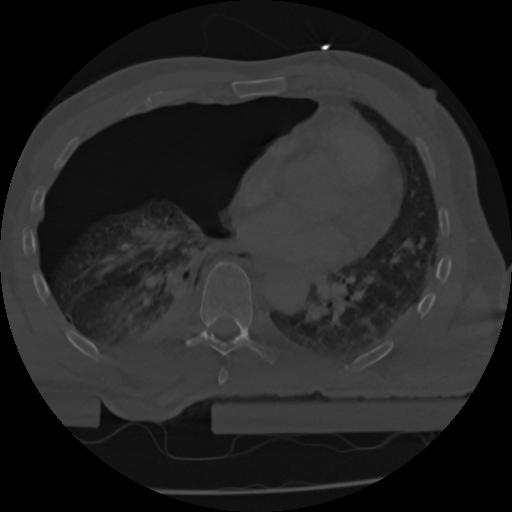

22 ANGIO,CE,Vol,0.5,ANGIO,,